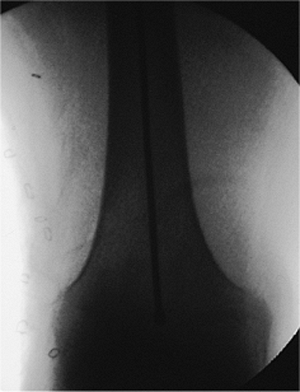

![]() |

Figure 21.2. AP radiograph of the right femur showing a transverse mid-diaphyseal fracture with minimal comminution.